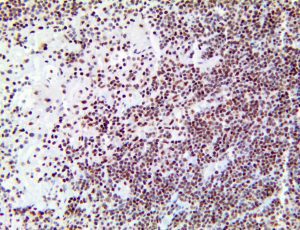

It is the ICU physician who is most likely to witness one of the deadliest manifestations of the abnormal immunological response, the cytokine storm syndrome (CSS). This response is also referred to by some as the cytokine release syndrome (CRS). CSS is characterized by continuous activation and expansion of macrophage and lymphocyte populations, which secrete large amounts of cytokines, causing the cytokine storm. This massive cytokine release is akin to hemophagocytic lymphohistiocytosis (HLH) disease, a syndrome characterized by initial unchecked and persistent activation of cytotoxic T lymphocytes and NK cells.

Clinical and laboratory manifestations of HLH include fever, enlarged liver and/or spleen, neurologic dysfunction, coagulopathy, liver dysfunction, cytopenias (i.e., low levels of erythrocytes, leukocytes, and/or platelets), hypertriglyceridemia, hyperferritinemia, hemophagocytosis, and eventually diminished NK cell activity as the immune system becomes progressively paralyzed. HLH can be familial (primary HLH) or secondary to another disease process (sHLH), such as rheumatic disease, in which it is referred to as macrophage activation syndrome (MAS, characterized by elevated ferritin).